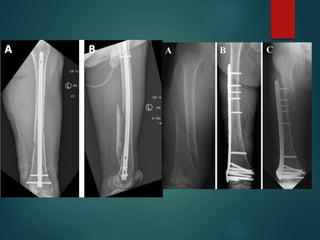

Tibial Shaft Fractures

 Treatment Options

 IM Nail

 ORIF with Plates

 External Fixation

 Cast or Cast-Brace

 Advantages of IM nailing

 Lower non-union rate

 Smaller incisions

 Earlier weightbearing and function

 Single surgery

 IM nailing of distal and

proximal fx

 Can be done but requires

additional planning, special

nails, and advanced

techniques

Tibial Pilon Fractures

 Fractures involving distal tibia metaphysis and into the ankle joint

 Soft tissue management is key!

 Often occurs from fall from height or high energy injuries in MVA

 “Excellent” results are rare, “Fair to Good” is the norm outcome

 Multiple potential complications